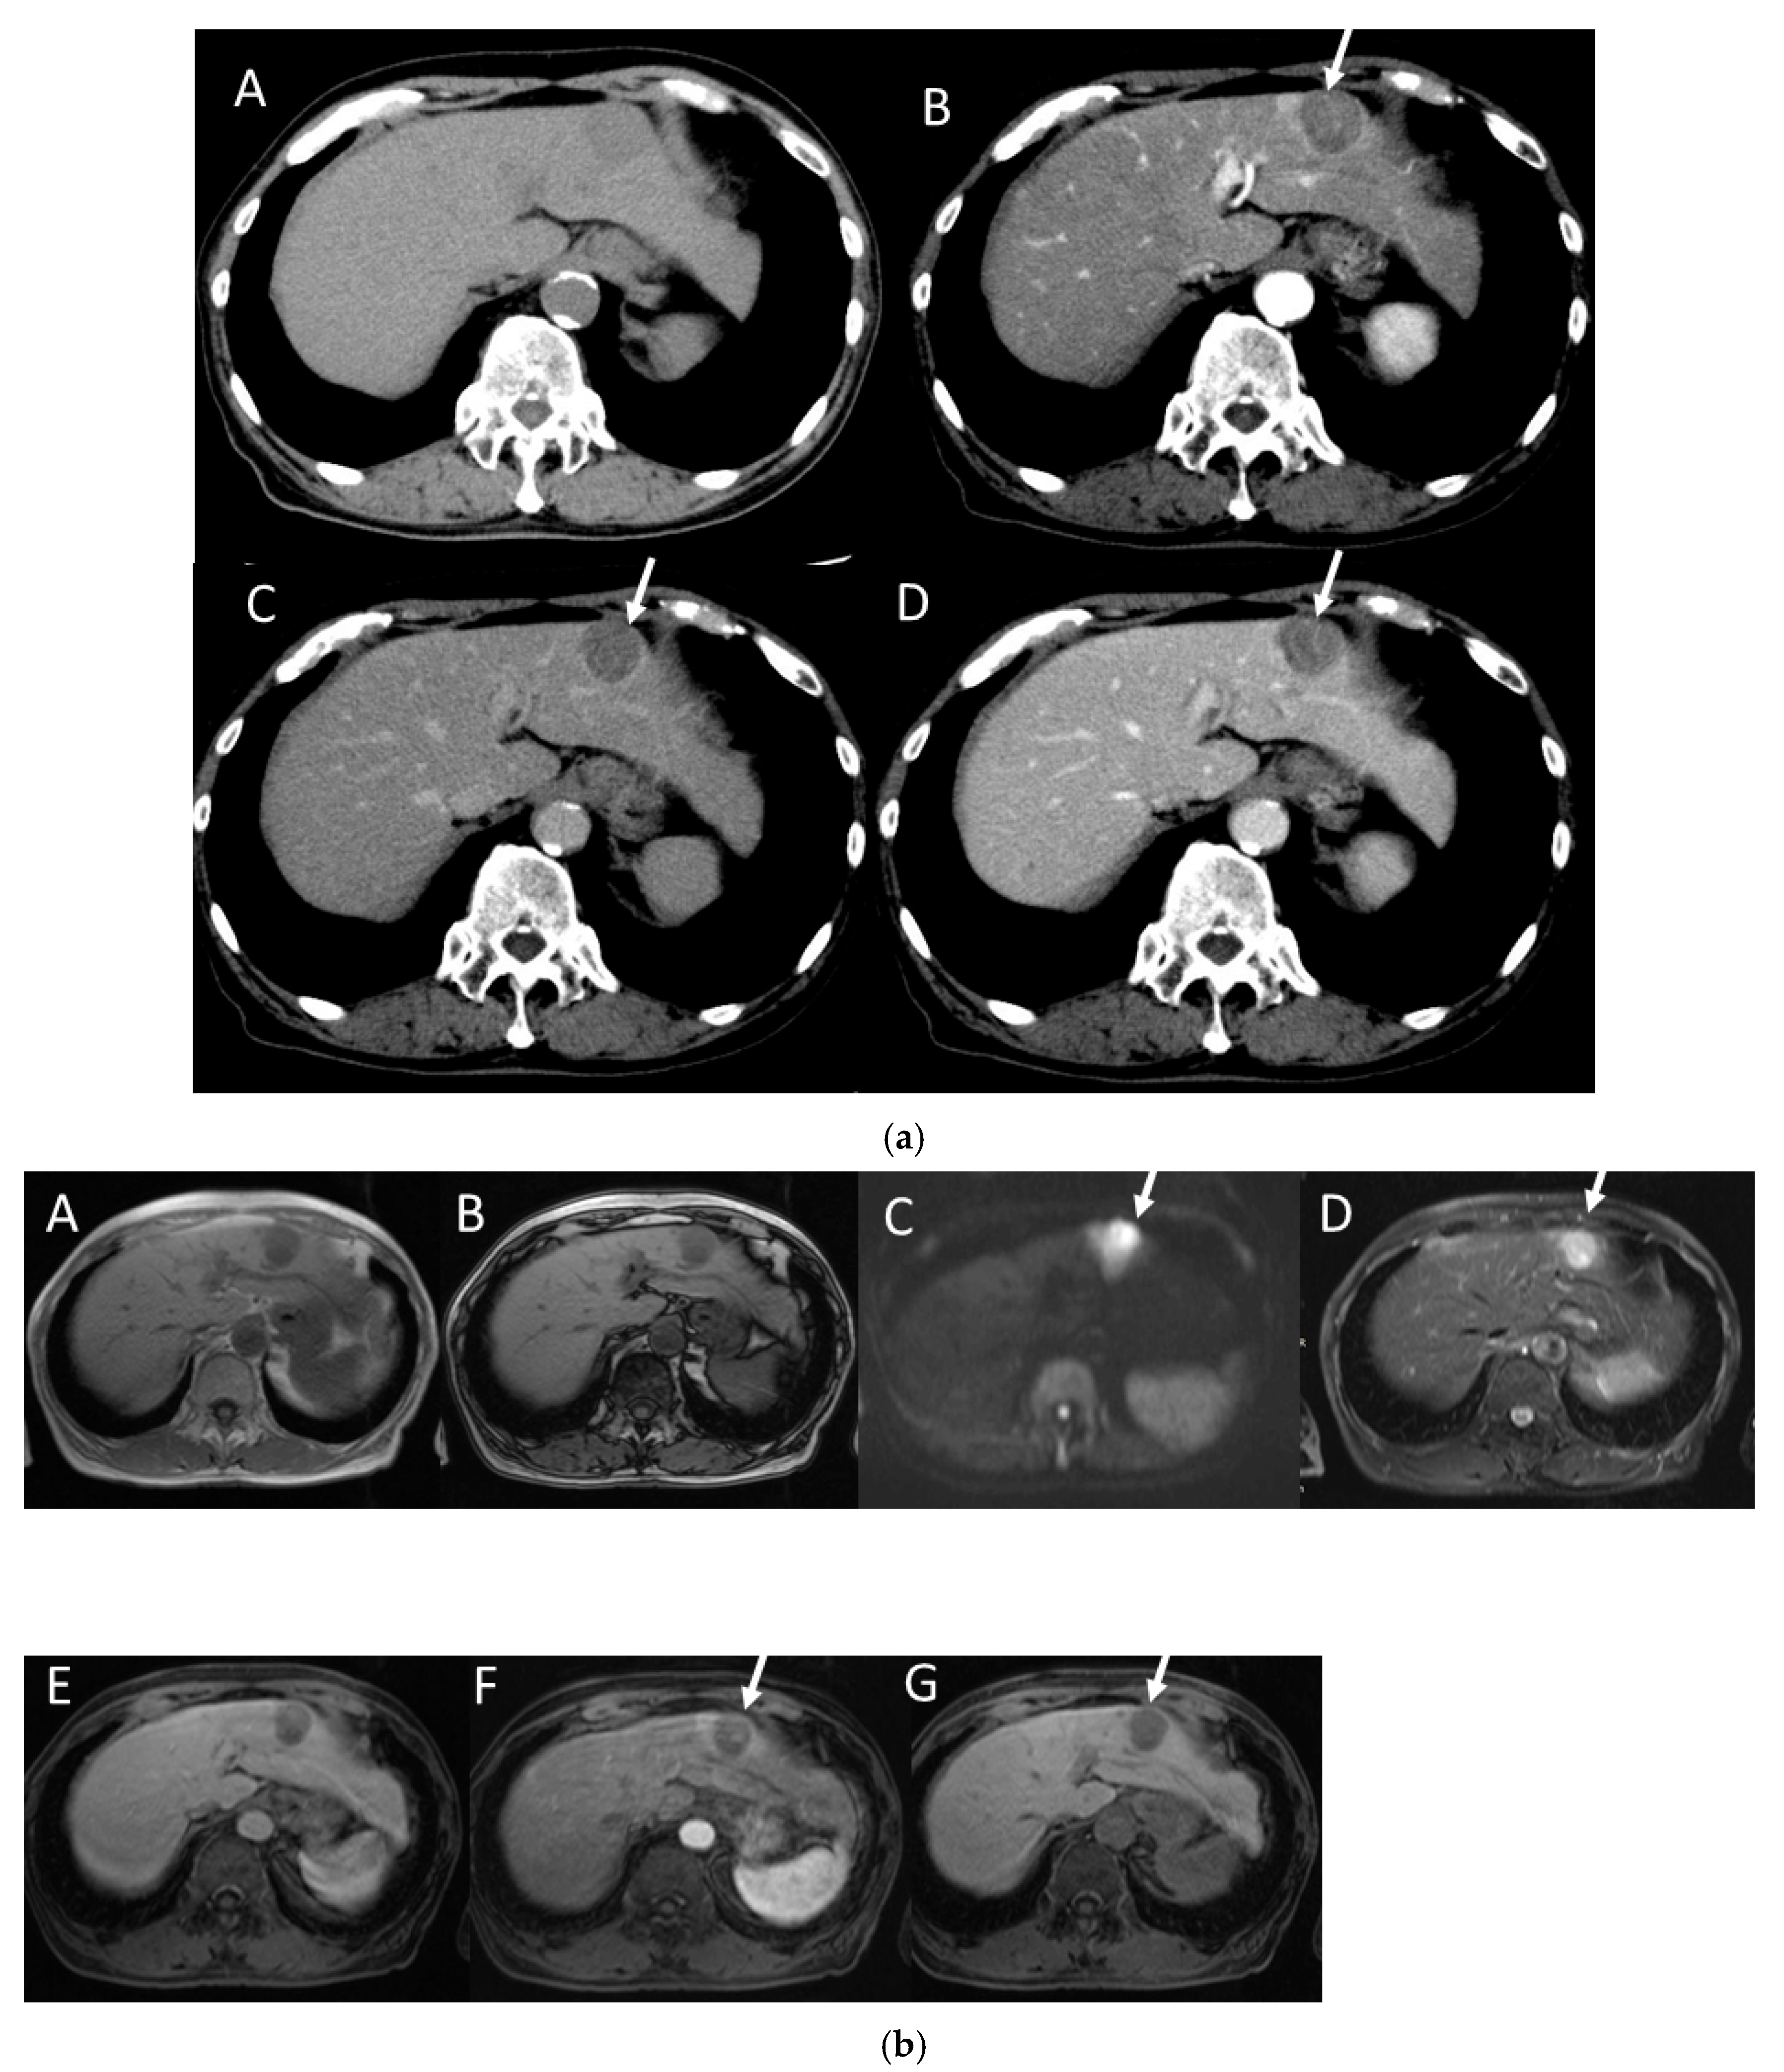

4.4. Moderately Differentiated Hepatocellular Carcinoma (Moderately HCC)

4.5. Poorly Differentiated Hepatocellular Carcinoma (Poorly HCC)